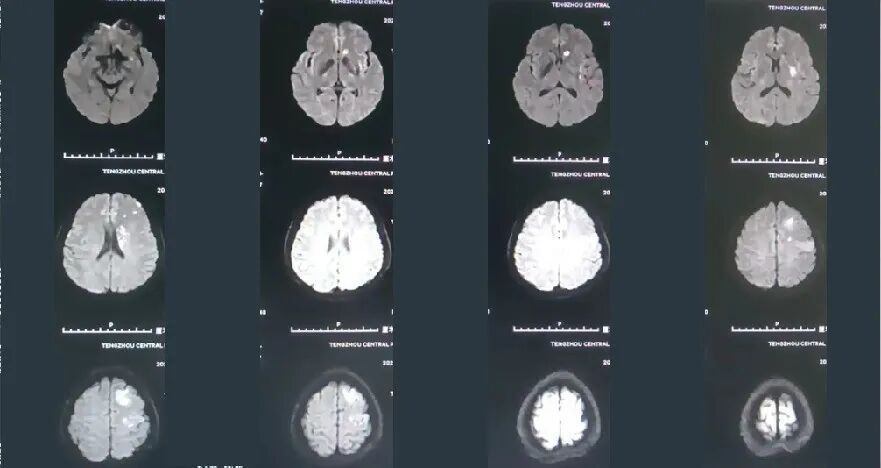

入院影像检查

导丝怎么扩【载药时代 球扩天下】NOVA DES®颅内药物洗脱支架在颈内动脉颅内段重度狭窄的应用两例!滕州市中心医院&山西医科大学第二医院_https://www.jmylbn.com_新闻资讯_第13张

2022-10-28,DWI

导丝怎么扩【载药时代 球扩天下】NOVA DES®颅内药物洗脱支架在颈内动脉颅内段重度狭窄的应用两例!滕州市中心医院&山西医科大学第二医院_https://www.jmylbn.com_新闻资讯_第14张

MRA

导丝怎么扩【载药时代 球扩天下】NOVA DES®颅内药物洗脱支架在颈内动脉颅内段重度狭窄的应用两例!滕州市中心医院&山西医科大学第二医院_https://www.jmylbn.com_新闻资讯_第15张

DSA:右侧颈内动脉正侧位

重要影像结论:右侧颈内动脉C6段狭窄约90%,长度约0.97cm。